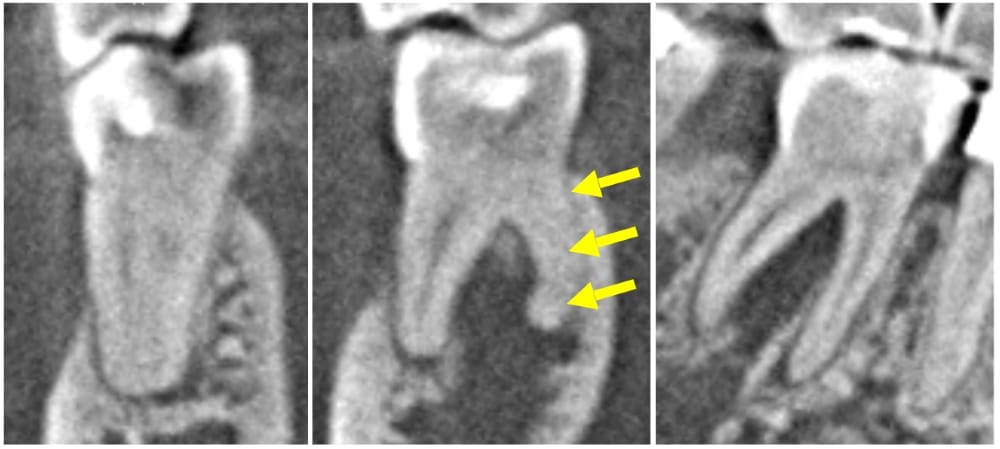

初診来院時の状態 CTによる三次元画像

CTを撮影すると、根尖周囲に大きな骨吸収像が認められます。また、下顎第一大臼歯に一定の確率で発現するRadix Entomolarisという遠心舌側根が認められました。この根管は、通常の根管よりも湾曲が強く、治療の難易度が高いことから、より慎重に治療を進める必要がある状態であると術前の状態から判断できました。